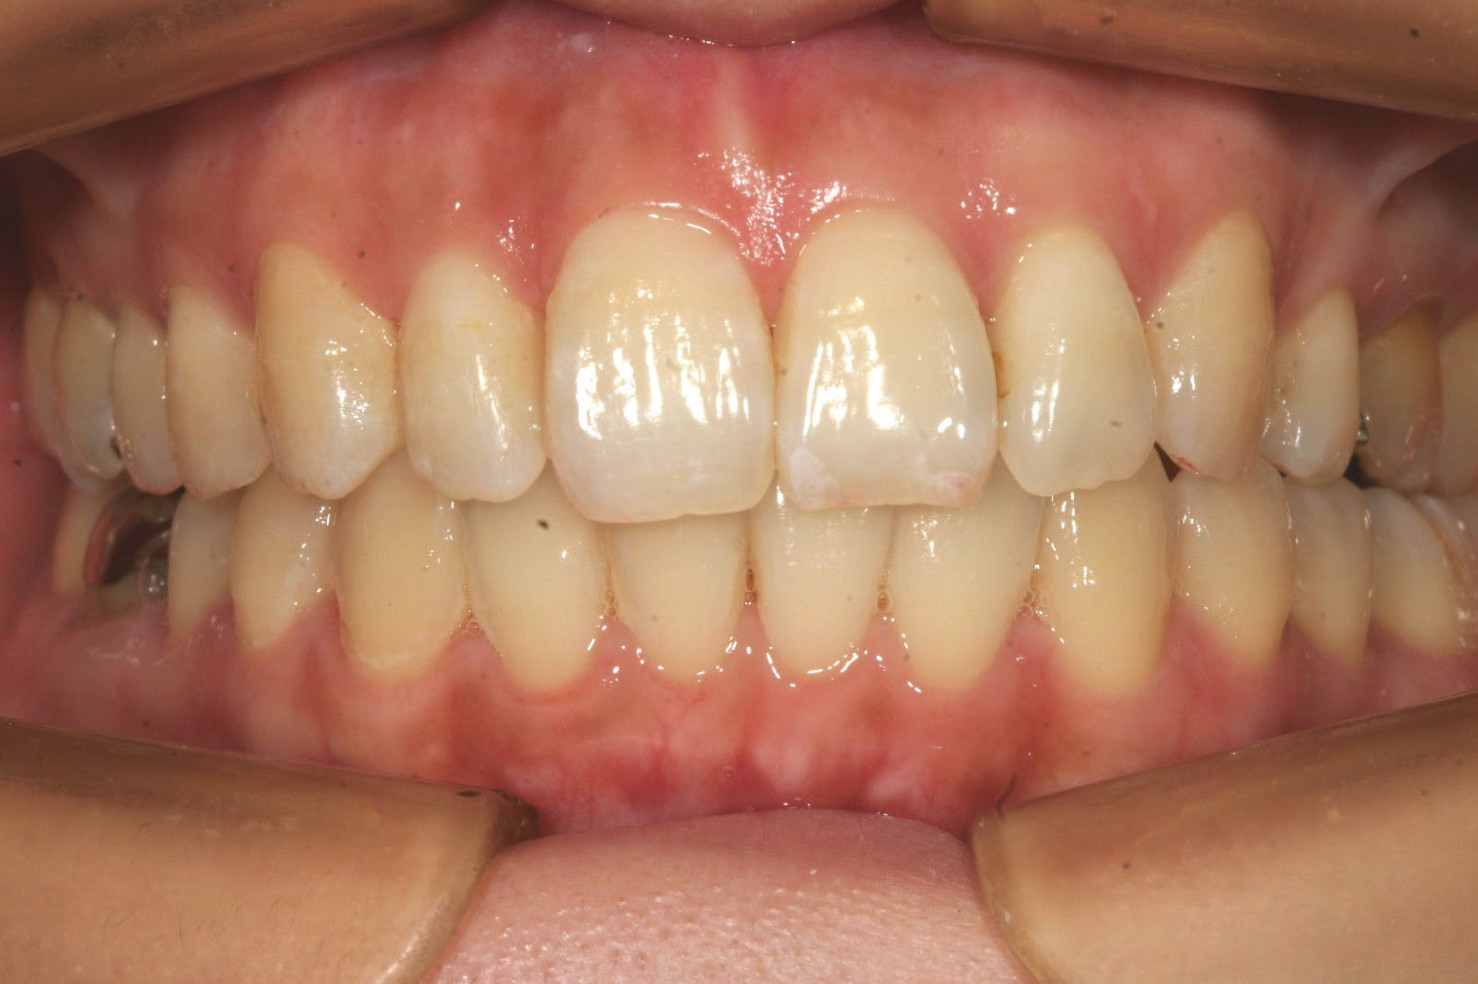

下顎のアーチは綺麗に並びました。

出っ歯観は完璧です。

今回は出っ歯観改善の為、左側上顎小臼歯を1本だけ抜歯しました。

あとは上顎の歯のねじれ改善、下顎の舌側転移も難なく出っ歯も改善しました。

リテーナーとして裏側からワイヤーで留めています。